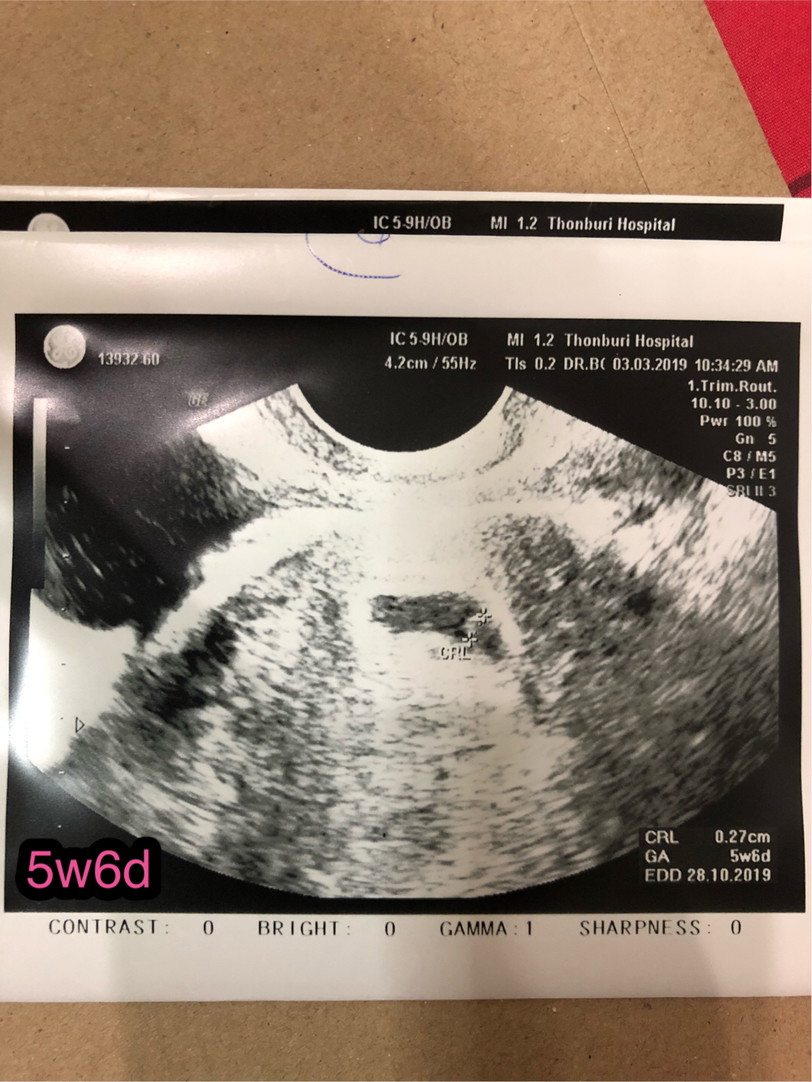

5w 6d 🥰🥰